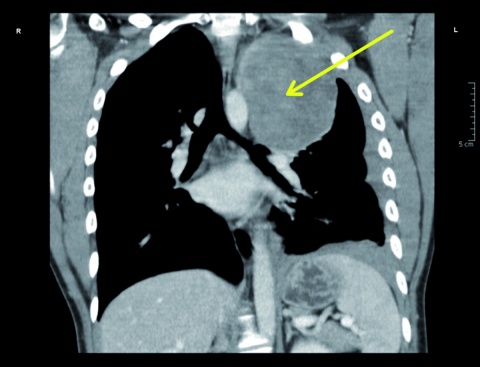

Fallbeispiel: Enchondrom

Zur Risikoklassifizierung von gutartigen Knochentumoren für die Beurteilung der allgemeinen Dienst- und Verwendungsfähigkeit von Soldaten Kevin Dallacker-Losensky¹, Magnus Scheer², Inken Seelmann¹, Michael Uhl³ ¹Sanitätsversorgungszentrum Volkach…